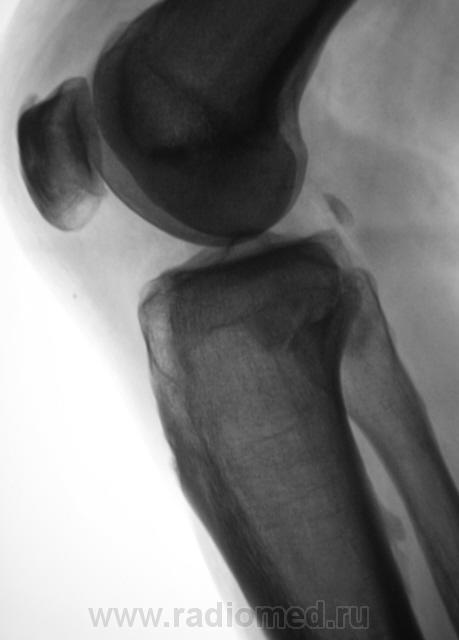

Мужчина средних лет, крепкий, ведущий активный образ жизни, занимающийся дозировано «элементами спорта», полковник милиции, в последнее время (несколько лет) почувствовал боли в области правого коленного сустава.

Энтезопатия надколенника, перегрузочная болезнь б/б кости(подозрение на неполный перелом).

Очень похожая картина на консолидированный перелом б\б кости. В проекции м\б кости определяется периостальная реакция или патологическая перестройка костной ткани.

Есть  признаки  артроза  и  синовита . Была  повреждена  передняя  крестообразная  связка.